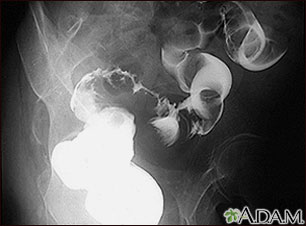

Rayos X de cáncer de colon sigmoide

Enema de bario en un paciente con cáncer del intestino grueso (área sigmoide).